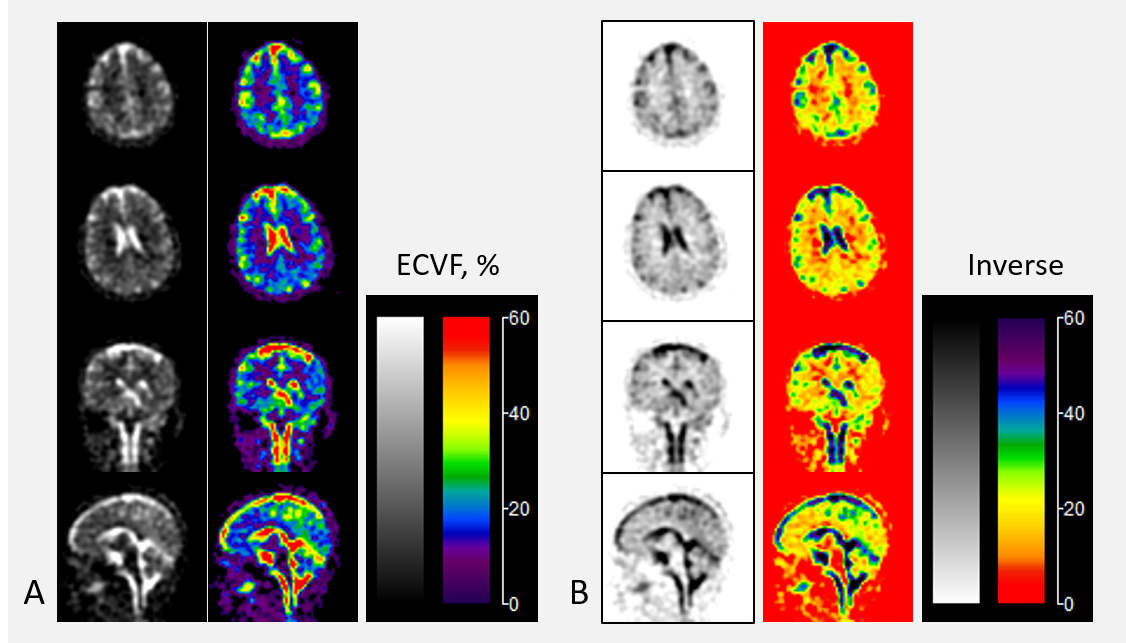

Extracellular Volume Change in Human Brains during Sleep: A Simultaneous Sodium (23Na) MRI and EEG Study

该研究探讨了睡眠期间人脑中细胞外体积的变化,使用同时进行的钠(23Na)MRI和脑电图(EEG)研究。研究者让参与者在MRI机器内尽可能放松并入睡,同时进行EEG记录。使用特定的MRI技术测量细胞外钠信号,以评估细胞外体积的变化。结果显示,在睡眠过程中细胞外体积发生了变化,但随着睡眠的加深,细胞外体积似乎有所减少,这与动物研究的发现相反。讨论部分指出,尽管研究结果表明睡眠期间细胞外体积有所变化,但这种变化的原因尚不清楚,需要进一步的研究来分析睡眠如何影响个体的细胞外体积。结论强调了需要更多的研究来验证这一观察结果,并探讨睡眠对细胞外体积影响的潜在机制。

31705f99b4dd40c73727155033e4e648.png

研究对象(43岁,女性)的细胞外体积分数 (ECVF) 代表性图,根据一次16分钟钠扫描的钠图像计算得出。反向对比度有助于突出显示ECVF值的白质区域。